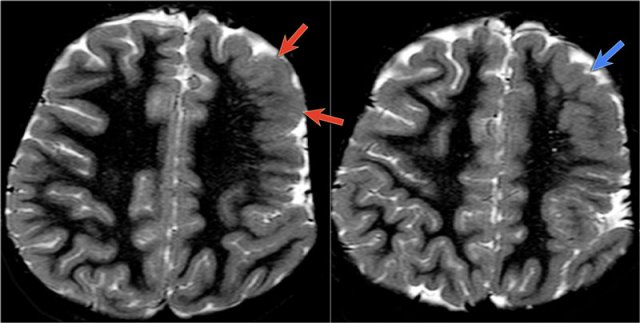

The images show typical focal cortical dysplasia.

There is cortical thickening and blurring of the grey/white matter junction on T1WI (left).

The FLAIR image on the right shows the subcortical hyperintensity.

The images demonstrate cortical and subcortical signal abnormalities on T2WI and FLAIR in the left temporal lobe indicating focal cortical dysplasia.

Notice associated T2/FLAIR hyperintense and shrunken hippocampus as a result of mesial temporal sclerosis, i.e. dual pathology.